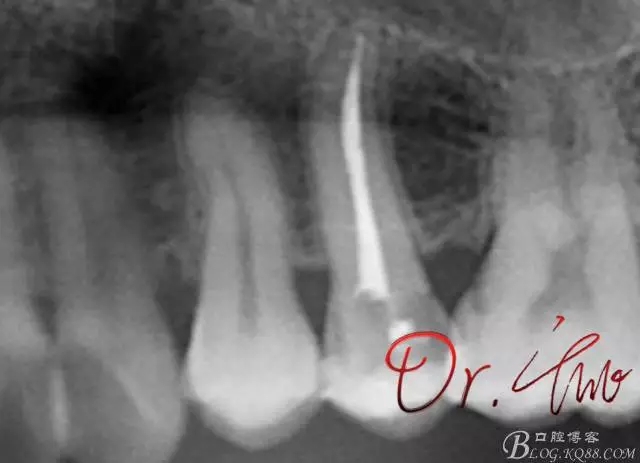

拍片確定長度

640.webp (1).jpg